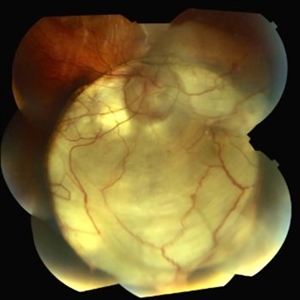

This 18-year-old woman has an optic nerve coloboma right eye with longstanding poor vision.

Photographer: Thomas Steele

Condition/keywords: coloboma of optic disc, coloboma of the optic nerve